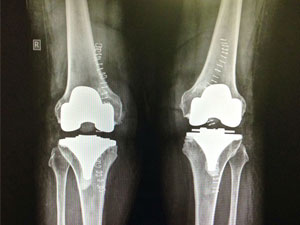

After Surgery